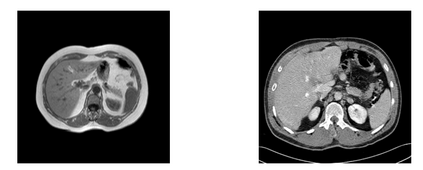

In many clinical settings, the use of both Computed Tomography (CT) and Magnetic Resonance (MRI) is necessary to pursue a thorough understanding of the patient's anatomy and to plan a suitable therapeutical strategy; this is often the case in MRI-based radiotherapy, where CT is always necessary to prepare the dose delivery, as it provides the essential information about the radiation absorption properties of the tissues. Sometimes, MRI is preferred to contour the target volumes. However, this approach is often not the most efficient, as it is more expensive, time-consuming and, most importantly, stressful for the patients. To overcome this issue, in this work, we analyse the capabilities of different configurations of Deep Learning models to generate synthetic CT scans from MRI, leveraging the power of Generative Adversarial Networks (GANs) and, in particular, the CycleGAN architecture, capable of working in an unsupervised manner and without paired images, which were not available. Several CycleGAN models were trained unsupervised to generate CT scans from different MRI modalities with and without contrast agents. To overcome the problem of not having a ground truth, distribution-based metrics were used to assess the model's performance quantitatively, together with a qualitative evaluation where physicians were asked to differentiate between real and synthetic images to understand how realistic the generated images were. The results show how, depending on the input modalities, the models can have very different performances; however, models with the best quantitative results, according to the distribution-based metrics used, can generate very difficult images to distinguish from the real ones, even for physicians, demonstrating the approach's potential.